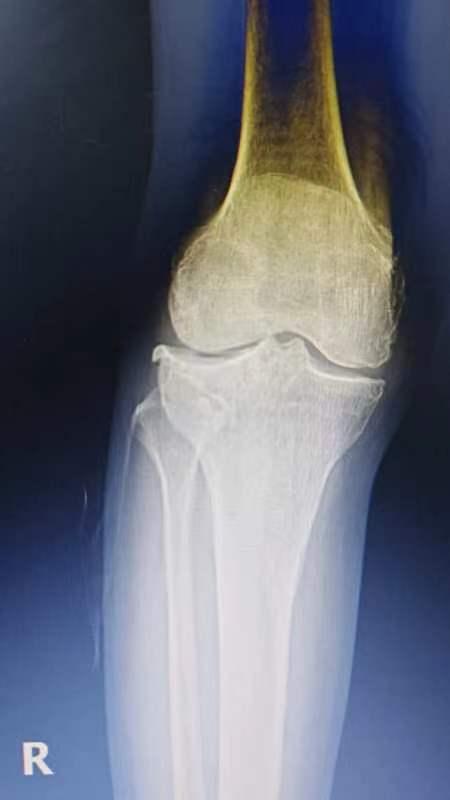

退行性骨关节炎,俗称“骨质增生”或“长骨刺”,是一种与年龄增长密切相关的关节疾病。其发病过程如下:随着年龄增长,或受关节受伤、基础疾病影响,关节软骨会逐渐退化、失去弹性,进而出现裂缝、糜烂甚至溃疡,表面变得粗糙;不光滑的软骨在关节活动中相互摩擦,会进一步加剧软骨损伤;当软骨完整性被破坏后,下方骨骼因失去保护而承受异常压力,便会通过增生形成“骨刺”来代偿,最终引发骨关节炎。